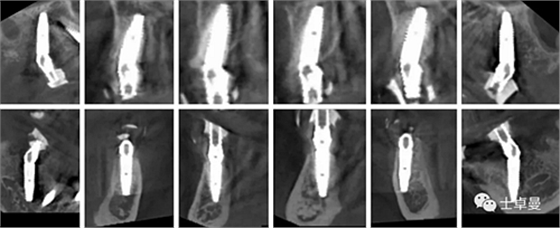

術(shù)前評估

種植術(shù)前從外科角度和修復角度對患者進行詳細的術(shù)前評估。

a4.png

a5.png